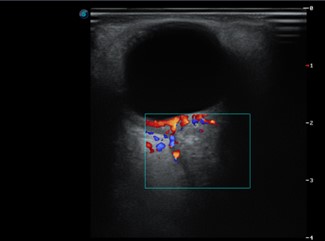

Imágenes E y F: ecografía ocular derecha: a nivel retroorbitario en el ojo derecho y en el área correspondiente a la inserción del nervio óptico, se observa una imagen asimétrica con relación al contralateral de ecoestructura sólida ubicada en la vaina del nervio óptico las medidas 11,7 x 9,8 mm.